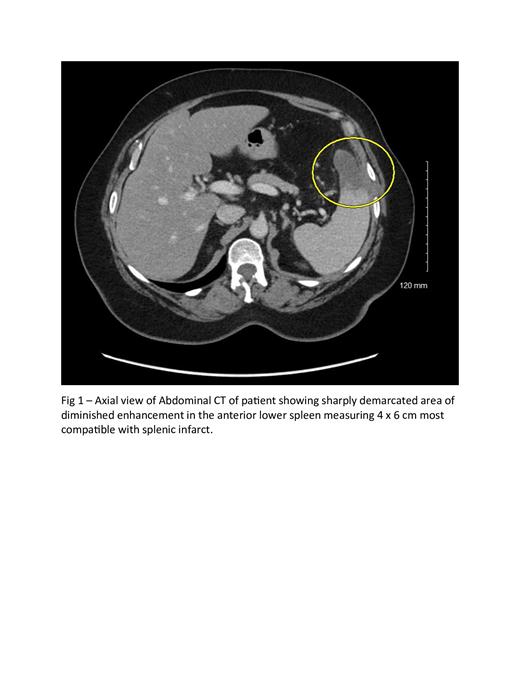

A 66-year-old Hispanic female who presented with left sided abdominal pain that gradually worsened over the course of 1 week; she believed it was stomach cramps. Laboratory evaluations were pertinent for platelet counts of 2000 x 10 9/L, hemoglobin level was 10.9 g/dl, and leukocytosis (white blood cell count 13.2k/uL) without left shift. Further work-up with iron studies was unremarkable and molecular studies were negative for BCR-ABL 1, PDGFR alpha/beta, FGFR 1, JAK2 V617F (including exons 12-13), CALR and MPL. A bone marrow biopsy showed an increase in megakaryocytes with some atypical forms with “enlarged size and nuclear hyper lobulation, and mild patchy reticulin fibrosis” suggestive of myeloproliferative neoplasm. Computed Tomography of the abdomen and pelvis with contrast showed evidence of splenic infarct. The patient was started on oral aspirin 81mg and oral hydroxyurea 2000 mg daily. Due to poor response to hydroxyurea and aspirin, she eventually had two cycles of platelet apheresis, and her platelet count improved to 1000 x 10 9/L. A repeat bone marrow biopsy was subsequently done to confirm essential thrombocythemia. At the time of discharge, the patient was asymptomatic and platelet count had decreased to 892 × 10 9/L.